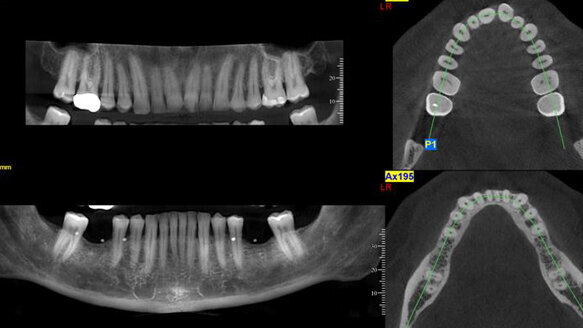

The machine Jarrin is referring to, which is installed in all the vans, is the NewTom VGi unit, a cone-beam scanning unit that can provide life-size cross-sectional images of the mandible and maxilla. It can be used for analysis of implants, TMJ, orthodontics, maxillofacial surgery and as an airway assessment essential for correcting obstructive sleep disorder.

“As far as the diagnostic results, the image quality from the NewTom VGi have been superb; nothing else even comes close. After a scan is performed, I get the images immediately and do a consultation with the patient. It’s fantastic.”